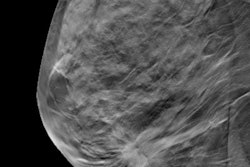

Digital breast tomosynthesis (DBT) exposed women to significantly less radiation than full-field digital mammography (FFDM) in a study of 200 patients published on June 3 in the Journal of Medical Radiation Sciences.

DBT is an increasingly popular breast screening method due to its high cancer detection rate and low number of false-positive rates, as well as lower call-back rates. However, there is some concern over radiation exposure with the modality.